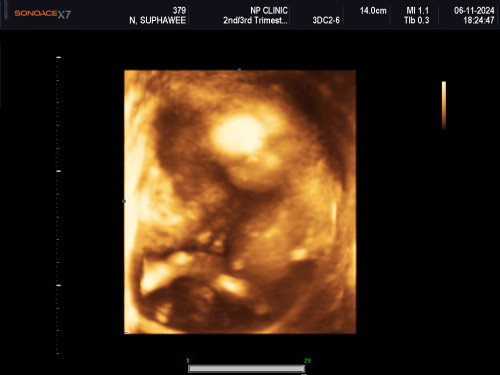

16week ++ ไปเจอมารอบนี้โตขึ้นเยอะเรย

น้องโตเยอะมากเรยยยยย อยากเจอเร็วๆจัง ภาพซาว4มิติ